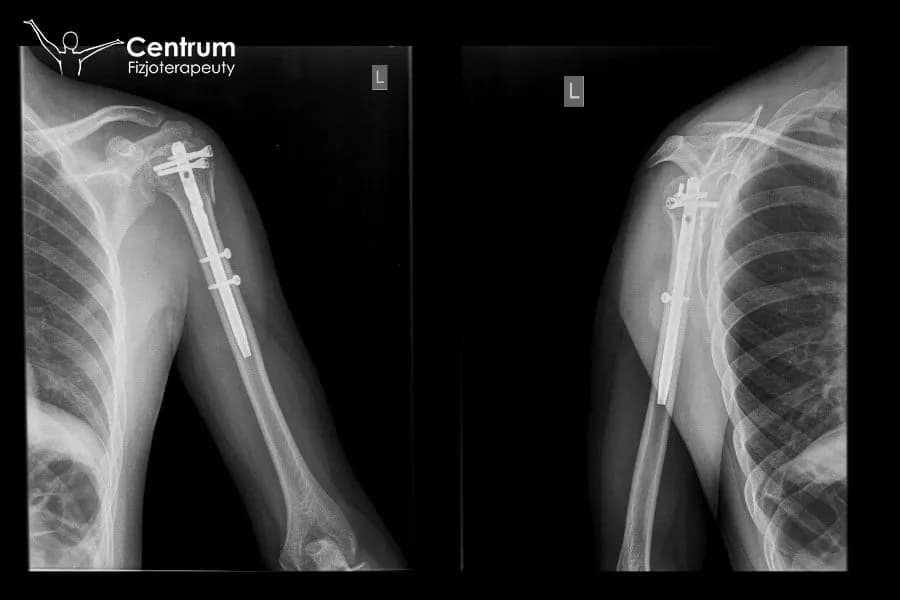

Decyzja o wyborze metody leczenia czy będzie to leczenie zachowawcze, polegające na unieruchomieniu kończyny, czy też interwencja chirurgiczna zapada na podstawie wielu czynników, takich jak typ złamania, jego stabilność, wiek pacjenta i jego ogólny stan zdrowia. W przypadku złamań stabilnych, bez przemieszczeń, często wystarczające jest unieruchomienie w ortezie lub gipsie. Natomiast złamania niestabilne, skomplikowane lub z dużym przemieszczeniem wymagają zazwyczaj operacji. Wybór tej ścieżki ma bezpośredni wpływ na to, kiedy i w jaki sposób rozpoczniemy rehabilitację po operacji często można zacząć delikatne ruchy wcześniej, ale sam proces może być bardziej złożony ze względu na ingerencję chirurgiczną.